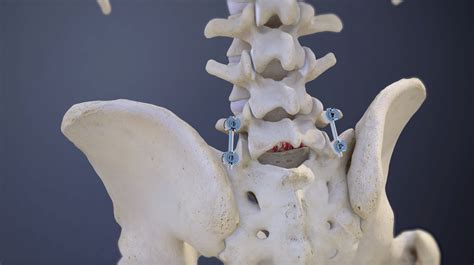

• Bone Grafting: Bone graft material is placed between the L4 and L5 vertebrae to promote fusion.

• Instrumentation: Screws, rods, or cages may be used to stabilize the vertebrae and hold them in place while the fusion heals.